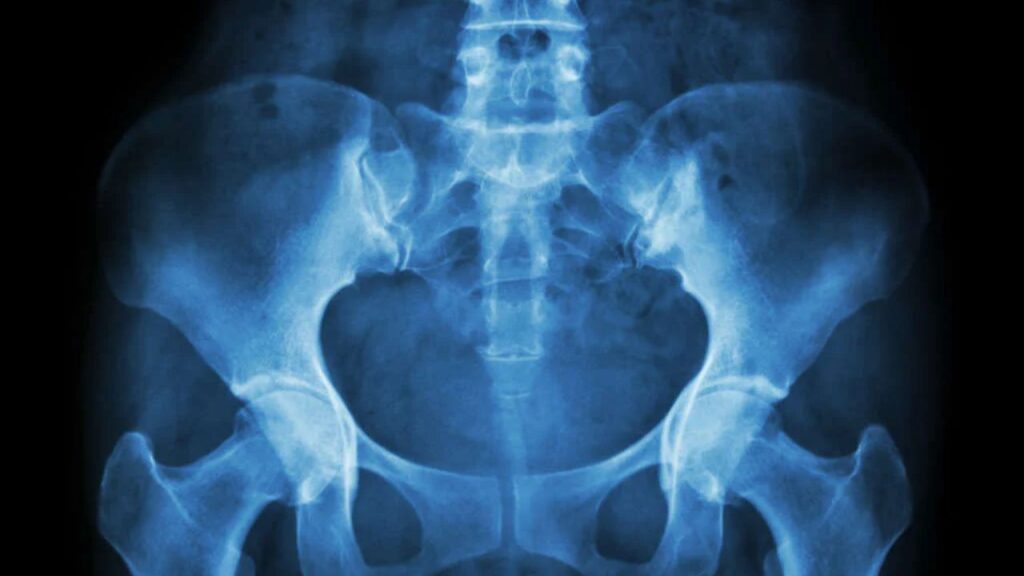

Diagnóstico preciso O diagnóstico é feito pela combinação do exame clínico, com manobras específicas que provocam a dor na articulação sacroilíaca, e exames de imagem. Radiografias podem mostrar sinais de artrose ou inflamação crônica, mas a ressonância magnética é o exame mais sensível para detectar a inflamação (edema ósseo) precocemente e avaliar as estruturas adjacentes em detalhe.